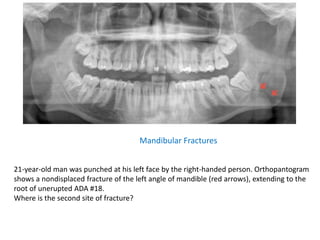

21-year-old man was punched at his left face by the right-handed person. Orthopantogram

shows a nondisplaced fracture of the left angle of mandible (red arrows), extending to the

root of unerupted ADA #18.

Where is the second site of fracture?